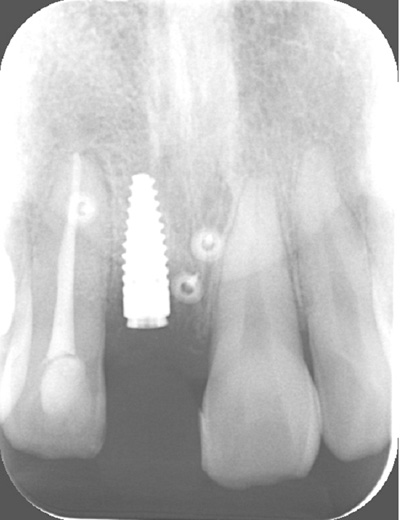

| 年代・性別 | 30代 男性 |

|---|---|

| 主訴 | 前歯が腫れた |

| 治療期間 | 約18ヶ月 |

| 費用 | 700,000円 |

| 治療内容 | インプラント、部分矯正、骨造成、結合組織移植、セラミック修復 |

| 治療に伴うリスク | インプラント周囲炎 セラミックの破折、脱離 |

*キャンセルポリシーをご一読のうえご予約ください